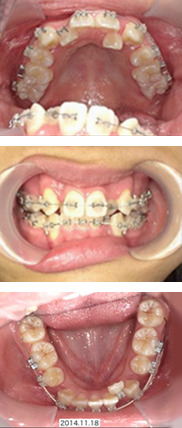

全体矯正症例

16才 女性

顎の成長が終了してから抜歯を行い、スペースを確保してそこにゆっくりと歯を移動させていきます。

歯並びも咬み合わせも整い、無事に矯正装置を外すことができました。

矯正前

矯正中

矯正後